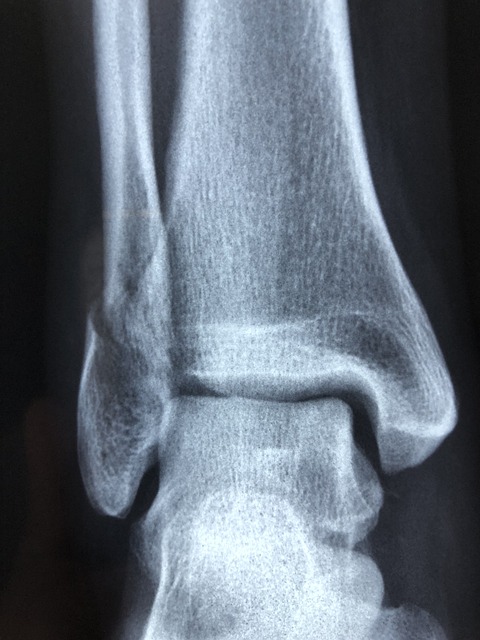

3) 잦은 골절

특히 엉덩이, 손목, 척추의 뼈는 사소한 넘어짐이나 약간의 충격에도 쉽게 부러질 수 있습니다.